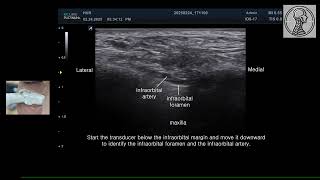

Ultrasound Of The Infraorbital Foramen. Courtesy...

30

0:55